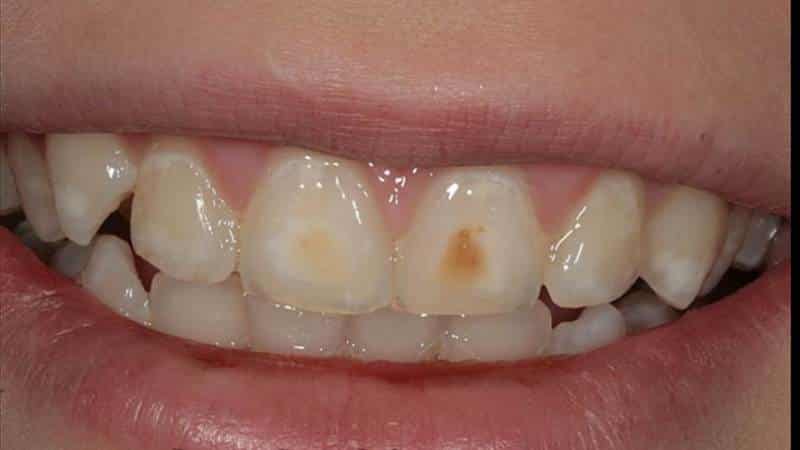

Некариозные поражения также могут включать флюороз, который возникает в результате избыточного потребления фтора в период формирования зубов. Клинически флюороз проявляется в виде белых пятен, полос или коричневых пятен на зубах, что может негативно сказываться на эстетике улыбки и вызывать повышенную чувствительность зубов.

Кроме того, следует упомянуть о гипоплазии эмали, которая представляет собой недостаток минерализации эмали в процессе ее формирования. Это состояние может быть вызвано различными факторами, включая генетические предрасположенности, инфекции или недостаток питательных веществ. Гипоплазия проявляется в виде участков с измененной текстурой и цветом эмали, что также может привести к повышенной чувствительности зубов и их предрасположенности к кариесу.